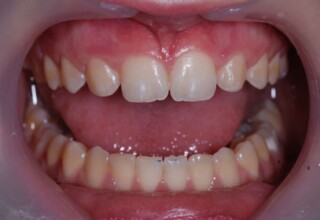

Whitening of non-vital teeth

Teeth with a root canal often lose their brightness and darken to an unesthetic level. Their bleaching requires an excellent root canal and patience. An adhesive filling is placed inside the root to confine the bleaching effect to the tooth part which is visible in the oral cavity. The actual bleaching may require 1-5 short sessions for the placement and renewal of the bleaching material. After the bleaching a high quality adhesive filling is mandatory.

Initial appearance

Final appearance